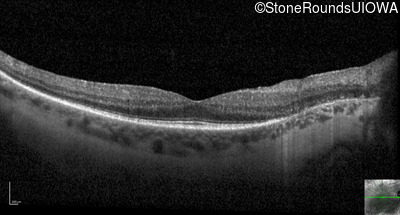

Optical Coherence Tomography - Right - 20/32

Exemplar / OCT Stack

OCT Stack